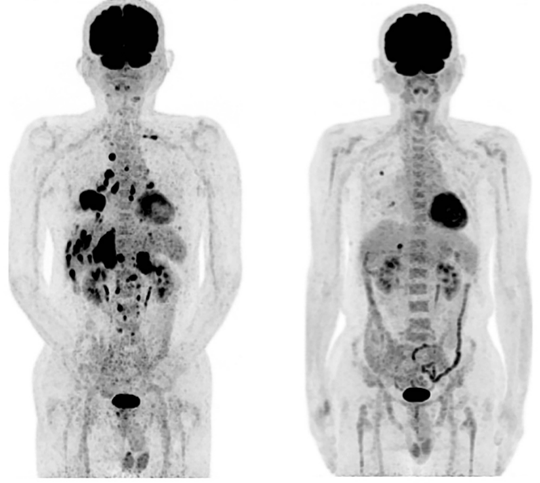

左侧(治疗前):诊断时的PET-CT显示除右下肺原发肿瘤外,还显示多发性双侧肺内转移、多发性肝转移、双侧肾上腺转移和多发性骨转移。

右侧(治疗后):第479天全身PET-CT,显示右肺有两个小转移,肝脏有一个。